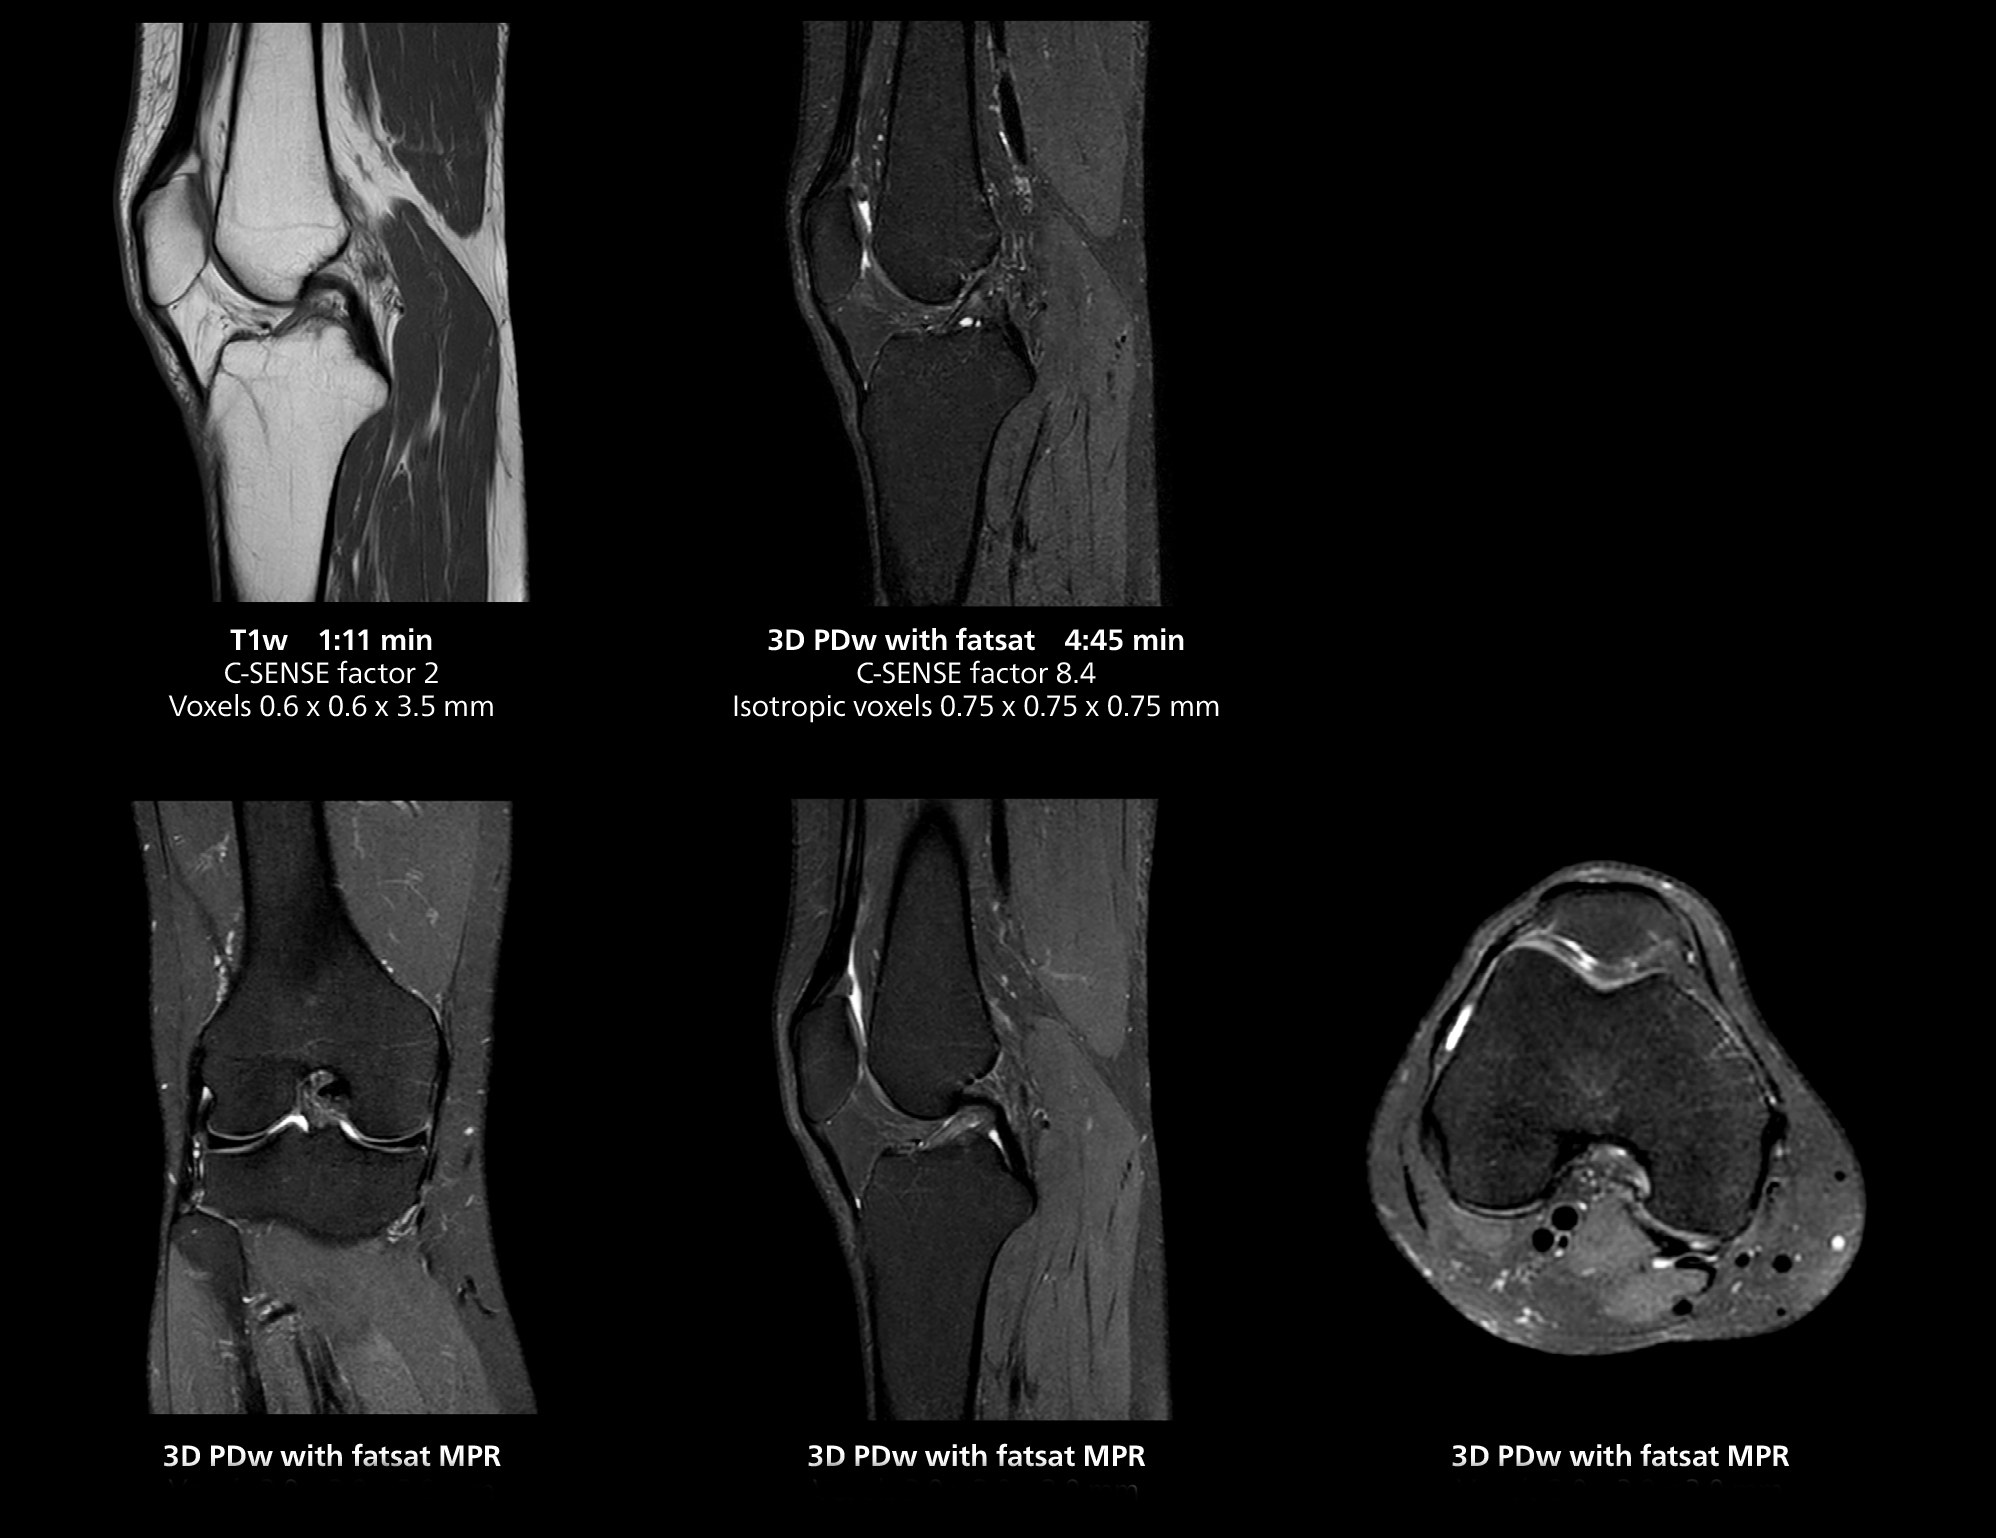

3D knee imaging

The isotropic high resolution 3D sequence in this MRI case allows for reformatting to obtain other orientations with high quality. Acquired on the MR 5300 system.